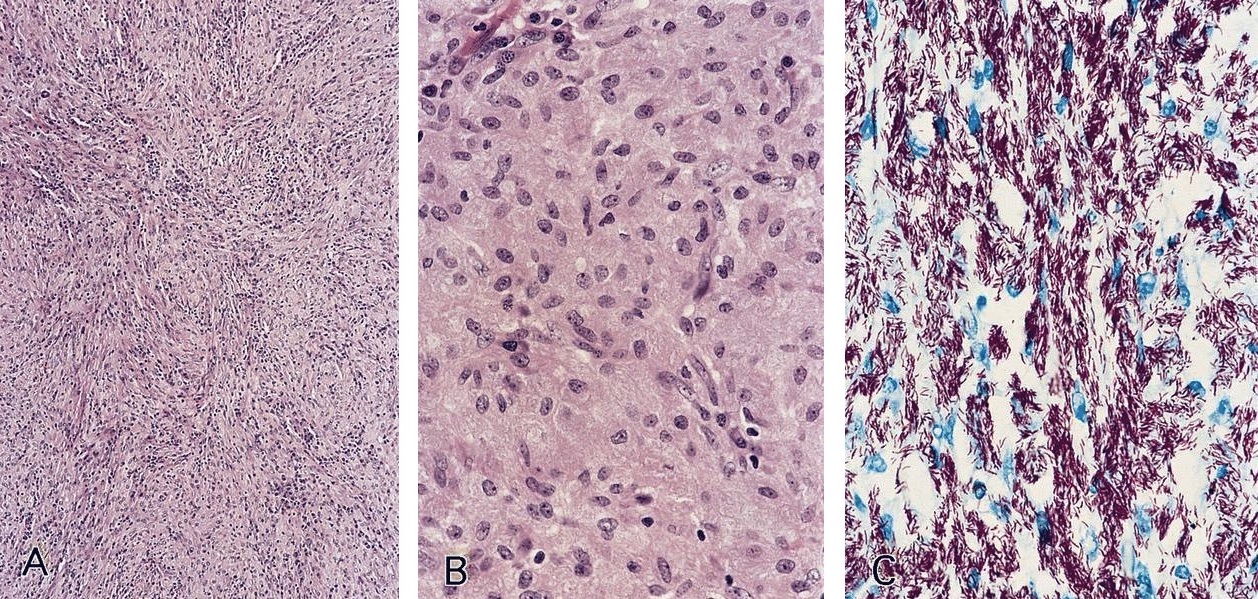

Microscopic (histologic) images

Contributed by AFIP and Chunyu Cai, M.D., Ph.D. (Case #532)

Microscopic (histologic) description

- Nodes show partial / complete effacement by storiform pattern of bland spindle cells, some with vacuoles

- Numerous vessels lined by plump endothelial cells, plasma cells and lymphocytes

- No multinucleated tumor cells, no foamy histiocytes

Cytology description

- Spindle cell proliferation resembling Kaposi sarcoma; no foamy histiocytes (Acta Cytol 1995;39:125)